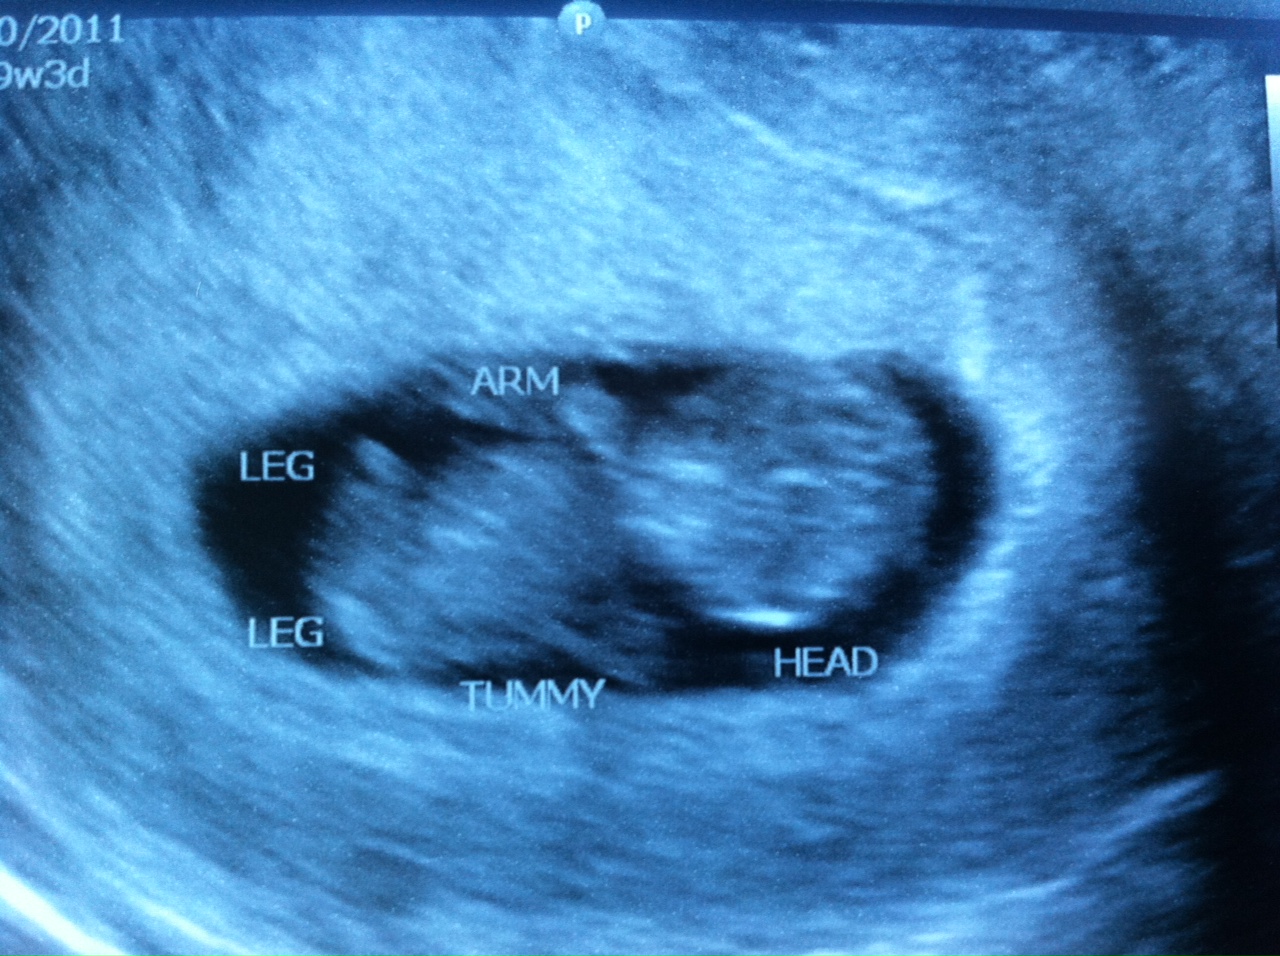

It’s already “Facebook official,” so I’m just catching up on the blog. Here’s the first picture of the littlest Wiard.

We are 10 weeks along and due on October 1st. Hannah is very excited about a baby coming. She is very nurturing toward younger kids and babies, so we are excited to see how she embraces her new role.